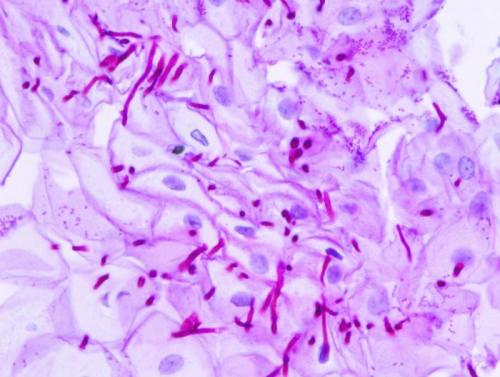

Мицелий при трихофитии выглядит как сплетение тонких нитей.

Они представляют собой гифы.

Внутри них визуализируются перегородки.

Они называются септами.

Лучше всего мицелий выявляется при обработке раствором КОН с концентрацией от 10 до 30%.

- Нити мицелия выявляют при изучении материала под микроскопом с использованием окрашивания образца. Такой анализ дает 80-процентную точность.